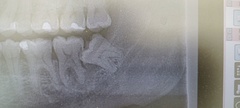

親知らずが半分生えた状態で痛みや腫れが起こる原因とは? 親知らずは、成長過程で最後に生える歯として知られていますが、その生え方に関しては個人差が大きく、正常に生えてくる場合もあれば、半分しか生えなかったり、斜めに生えてくることもあります。特に、親知らずが半分生えた状態で痛みや腫れが起きる場合、その原因を理解し、適切な対処をすることが非常に重要です。この記事では、親知らずが半分生えた状態で痛みや腫れが発生するメカニズムと、その解決策について詳しく説明します。 1.1 親知らずの生え方と歯茎の状態親知らずの正常な生え方とは?親知らずは、通常、18歳から25歳の間に生え始めます。理想的には、完全に直立して上下に並ぶことが理想的ですが、必ずしもそうならないのが現実です。親知らずは、下の歯茎の奥に、上の歯茎の奥にそれぞれ生えるのが一般的です。正常な生え方とは、歯が真っすぐに生えてきて、歯茎と歯の間に隙間がなく、歯磨きがしやすい状態です。 親知らずが斜めに生える場合の影響親知らずが斜めに生える場合、他の歯に圧迫をかけたり、歯茎に食べかすや細菌がたまりやすくなります。この状態が続くと、歯茎が炎症を引き起こし、痛みや腫れを伴うことが多いです。歯並びにも影響を与え、隣接する歯を押し出すことがあります。 1.2 歯茎にかぶさる親知らずが引き起こす問題親知らずの歯茎への圧迫親知らずが歯茎にかぶさることで、歯茎に圧力がかかり、炎症を引き起こします。この圧力が痛みや腫れの原因となります。また、歯茎が完全に開かずに親知らずが部分的に生えてくる場合、周囲の歯茎に隙間ができ、細菌が侵入しやすくなります。 歯茎がかぶさる状態のリスク親知らずの歯茎がかぶさる状態を「歯茎の炎症」と呼ぶことがあります。この状態では、歯茎が発赤し、腫れが起こりやすくなります。さらに、感染症が進行すると歯周病の原因になることもあり、最終的には歯の喪失にも繋がることがあるため、注意が必要です。 1.3 親知らずが原因で痛みや腫れが生じる理由親知らずが生えてくる過程で痛みや腫れを引き起こす主な原因は、歯茎に圧力をかけることによるものです。歯茎に圧迫が加わることで、炎症が発生し、その結果、痛みや腫れが現れます。また、親知らずが斜めに生えていると、隣接する歯や歯茎を圧迫するため、さらに痛みや腫れが強くなることがあります。